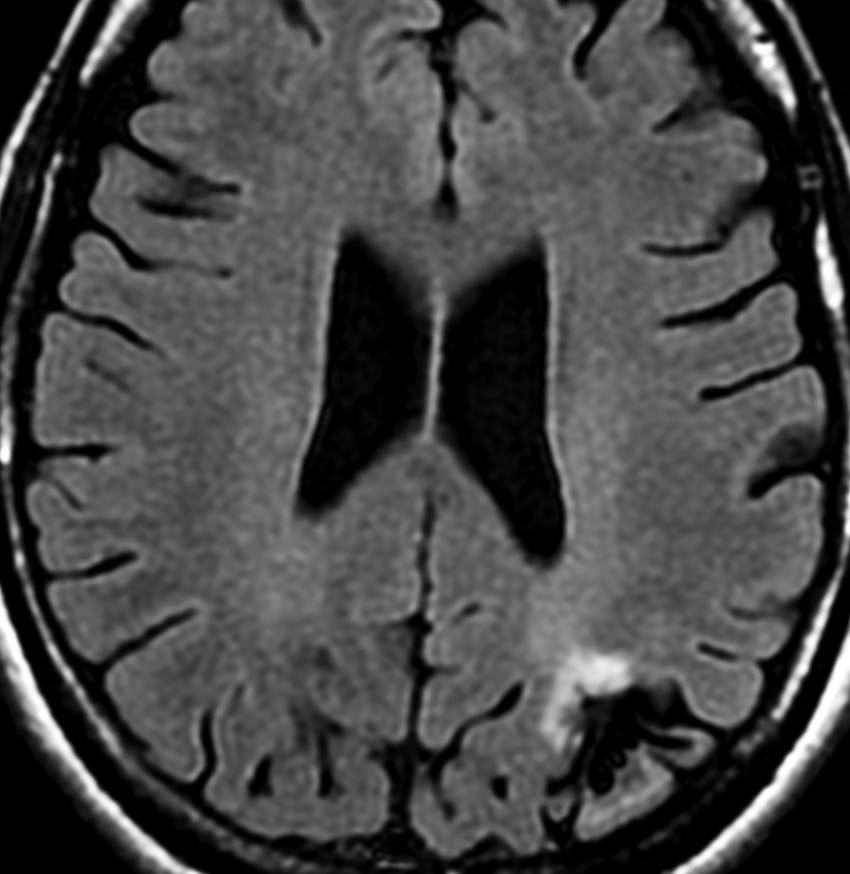

左側頭葉のびまん性星細胞腫です。左側のT1強調ガドリニウム像ではほとんど腫瘍は見えません。真ん中のT2強調画像でも見づらいです。右側のフレア画像で白くにじんでいるところに腫瘍があります。どこまでが腫瘍の境界なのかがはっきりしない腫瘍です。左の海馬(記憶の中枢)を侵し,とてもゆっくり大きくなるタイプで,この患者さんは10年以上治療をしないで経過を見ています。全摘出できない星細胞腫グレード2です。